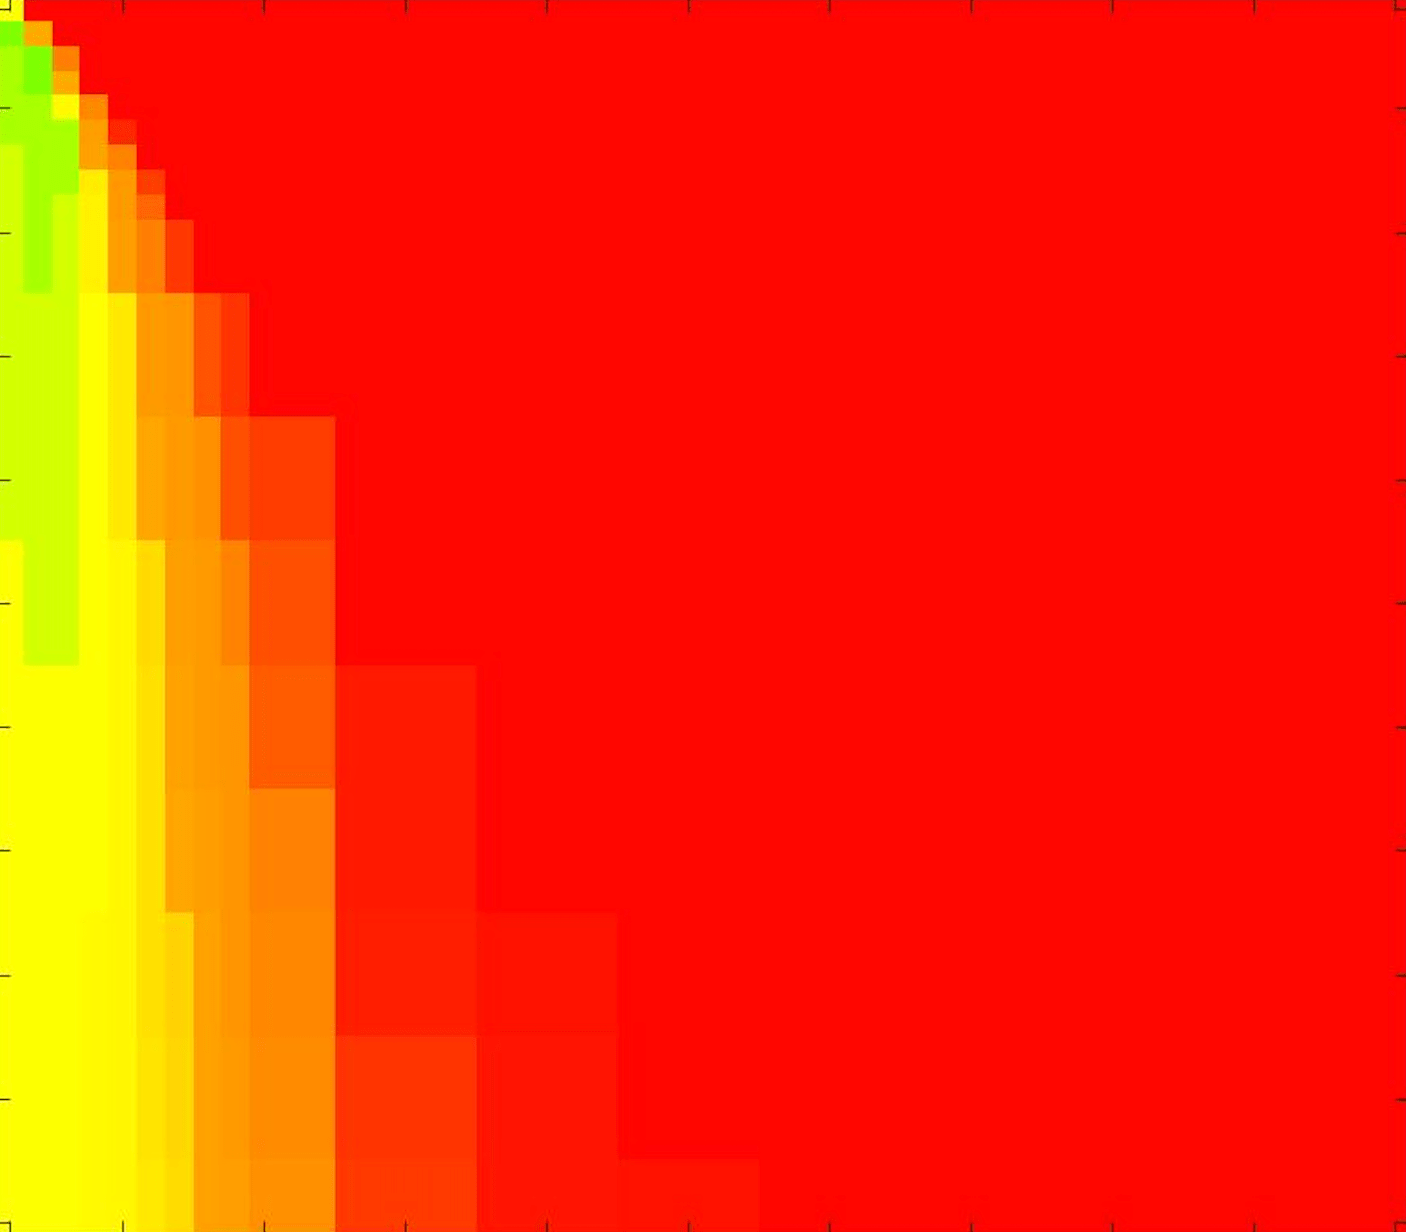

In these tests we aim to demonstrate how sensitive to parameter choices each choice of fitting term is. To accomplish this we perform the segmentations for each of the models discussed (CV, RSF, LCV, HYB, GAV) and the proposed model for a wide range of parameters and compute the TC value. The parameter range used is . Due to computational constraints, we run for each integer between 1 and 10, and every fifth from 15 to 50. This aspect of a model’s performance is vital when used in practice. The less sensitive to parameter choices a model is the more relevant it is in relation to potential applications. It should be noted that we neglect to test the selective models detailed in §3 with respect to parameter robustness as we are using the authors’ implementation of each approach. Instead, we make direct comparisons in the following sections.

The TC values for the parameter sets are presented as heatmaps in Figs. 11–13. A heatmap is a convenient way to display accuracy results for hundreds of tests concisely. In Fig. 9 we give an example heatmap with the same axes used for those in Figs. 11–13. For each of the combinations of parameter values we give the TC value of the segmentation result and represent it by the appropriate colour. The corresponding colour scale is shown in Fig. 8. Qualitatively, the more green areas of the heatmap the more accurate the model is for a wider set of parameters. Example results for Test Image 5 when varying (with ) for the proposed model are given in Fig. 10. Here it can be seen what each accuracy result corresponds to visually.

Synthetic Images. These results are presented in Fig. 11. For Test Images 1–2 we see poor parameter robustness from all competing models, except for GAV which performs reasonably well. However, the proposed model has minimal parameter sensitivity for these images, with good results achieved for almost every combination of values tested. For Test Image 3 all models have a reasonable parameter range (except for RSF), however the proposed model gives better quality results for a wider parameter range. The other models achieve reasonable results here as the foreground intensity of the ground truth is greater than the background , whereas for Test Images 1–2 they are equal . These results highlight the key advantage of the proposed model.

Real Images. In Fig 12 we present results for Test Images 4–6. Here, the proposed model performs in a similar way to its competitors because these images are more typical selective segmentation problems in the sense that there is a clear distinction between the foreground and background intensities. In particular, the values in each case are: Test Image 4 , Test Image 5 , and Test Image 6 . It can be seen that the proposed model is competitive compared to previous approaches. The performance is quite poor for Test Image 5, but is arguably still the best for this challenging case. In Fig. 13 we present results for Test Images 7–9. Here the proposed model outperforms previous approaches significantly for each image. This is mainly due to the type of image considered. Specifically, the true intensities are: Test Image 7 , Test Image 8 , and Test Image 9 . The proposed model is capable of achieving results where , with other models failing completely in these cases.